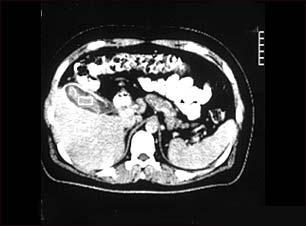

Litiaza biliara (calculii biliari)